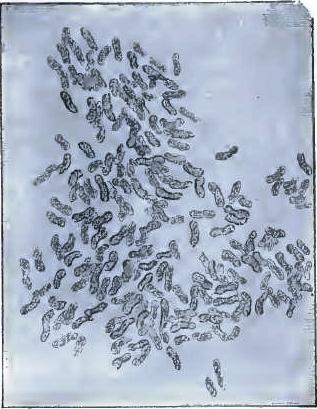

| FIGURE | |

| 7. | BACILLI FROM SWAMP-MUD |

| 8. | BACILLI FROM SEPTICÆMIC RABBIT |

| 9. | BACILLI FROM HUMAN SALIVA |

| 10. | BACILLUS ANTHRACIS |

| 11. | BACILLUS TUBERCULOSIS |